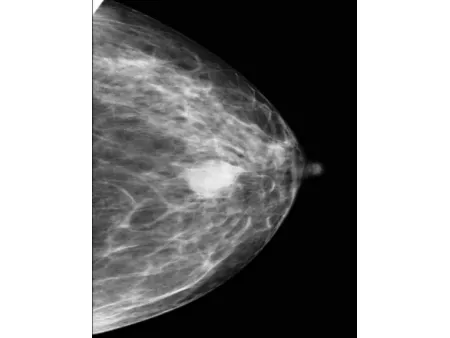

El detector plano CMOS, reconocido por su alta sensibilidad, permite obtener imágenes mamarias con gran nivel de definición. Este mamógrafo también incluye el software especializado Console, que utiliza algoritmos avanzados de posprocesamiento para mamografía, facilitando la visualización de estructuras finas y mejorando la precisión en la interpretación clínica. Con una capacidad de resolución de 60 líneas por centímetro, es capaz de detectar microcalcificaciones tan pequeñas como 0.1 mm, lo que refuerza su utilidad en programas de detección precoz de cáncer de mama y en evaluaciones clínicas más específicas.